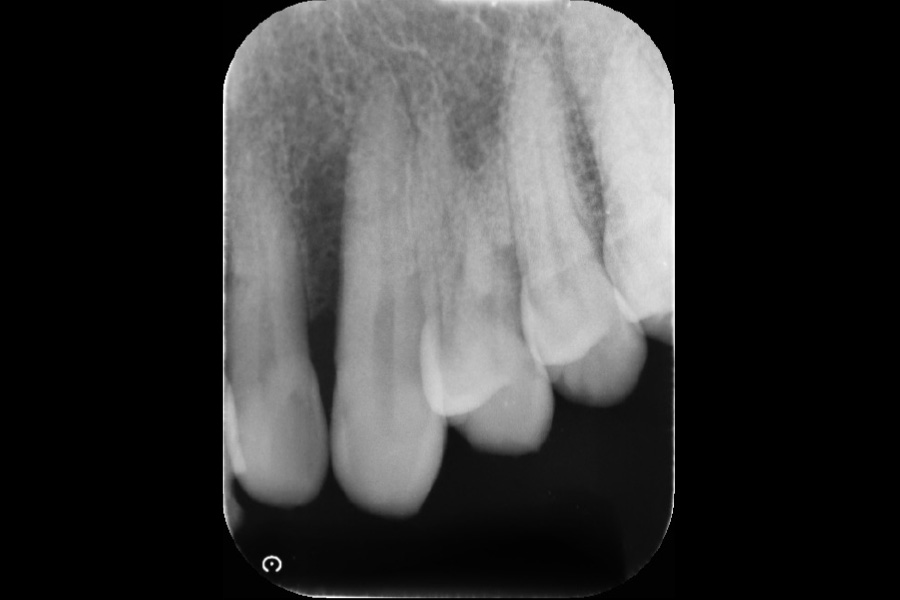

上の前歯の歯ぐきが腫れた

【歯周組織再生療法】

- 担当医

- 清水 宏康先生

- 主訴

- 上の前歯の歯ぐきが腫れた

- 期間

- 再生療法から再評価まで6か月

- 費用

- ¥220,000(税込)

- 治療内容

- 左上3近心に垂直性骨吸収が認められたためエムドゲインと骨補填材を用いて歯周組織再生療法を行った

- 治療に伴うリスク

- 歯肉退縮、知覚過敏